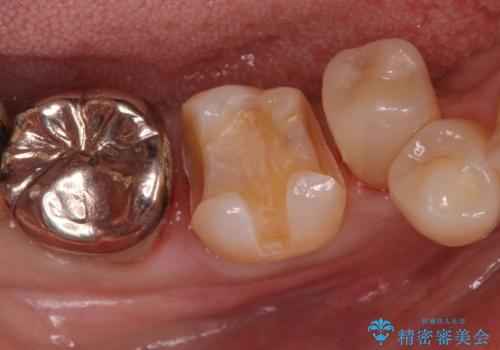

歯がかけた セラミックインレーでの治療

- 歯がかけたとのことで来院されました。

銀歯も白く作り替えたいとのことでしたのでセラミックインレーでの修復処置を行います。